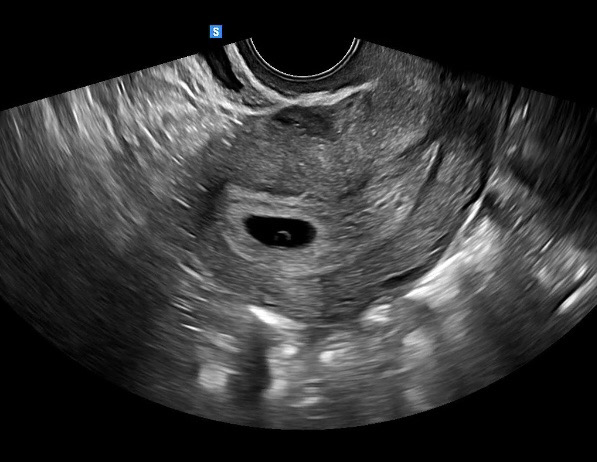

이게 난황이 맞을까요??

배란+25일인 이번주 월요일 병원에서 초음파 보고왔는데 선생님이 난황낭? 이라고 표현하시던데 이게 다들 말씀하시는 그 난황이 맞나요?? 2주뒤 애기 심장소리 들려야한다구 그때 보자고 하시던데 잘 크고 있는거겠죠~?

난황 같아요!!